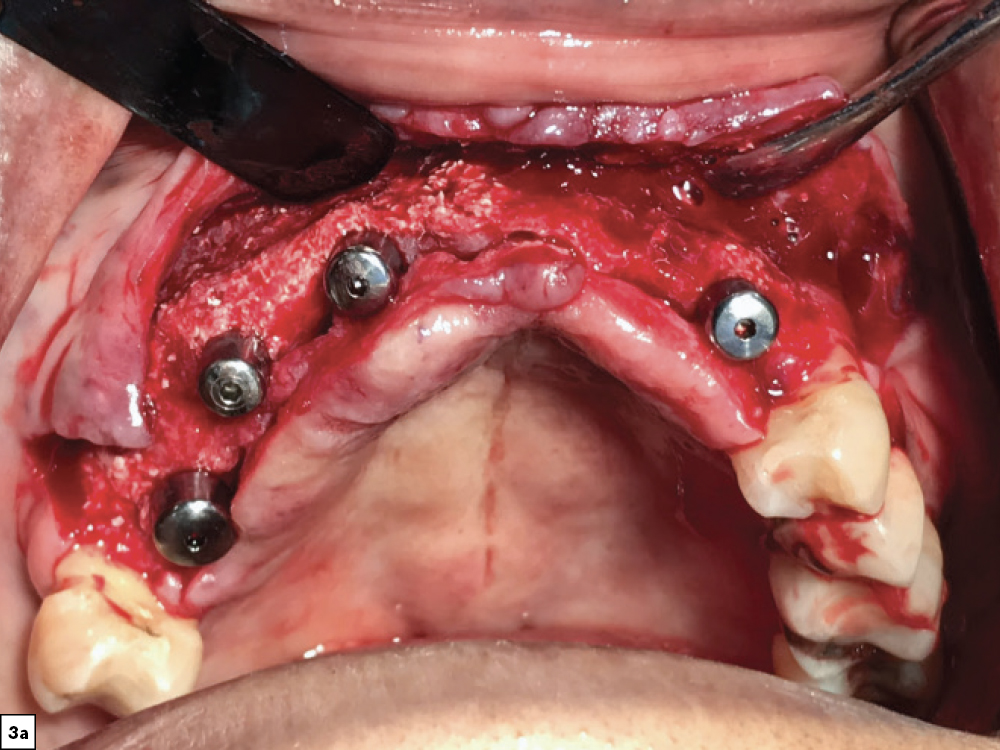

Figures 3a, 3b: After four months of healing, the patient returned for evaluation and exhibited sufficient bone volume for implant placement. After reflecting a full-thickness periosteal flap with vertical releasing incisions, four implants were placed. Healing abutments were connected to the implants, additional grafting material was placed and the surgical flap was sutured.